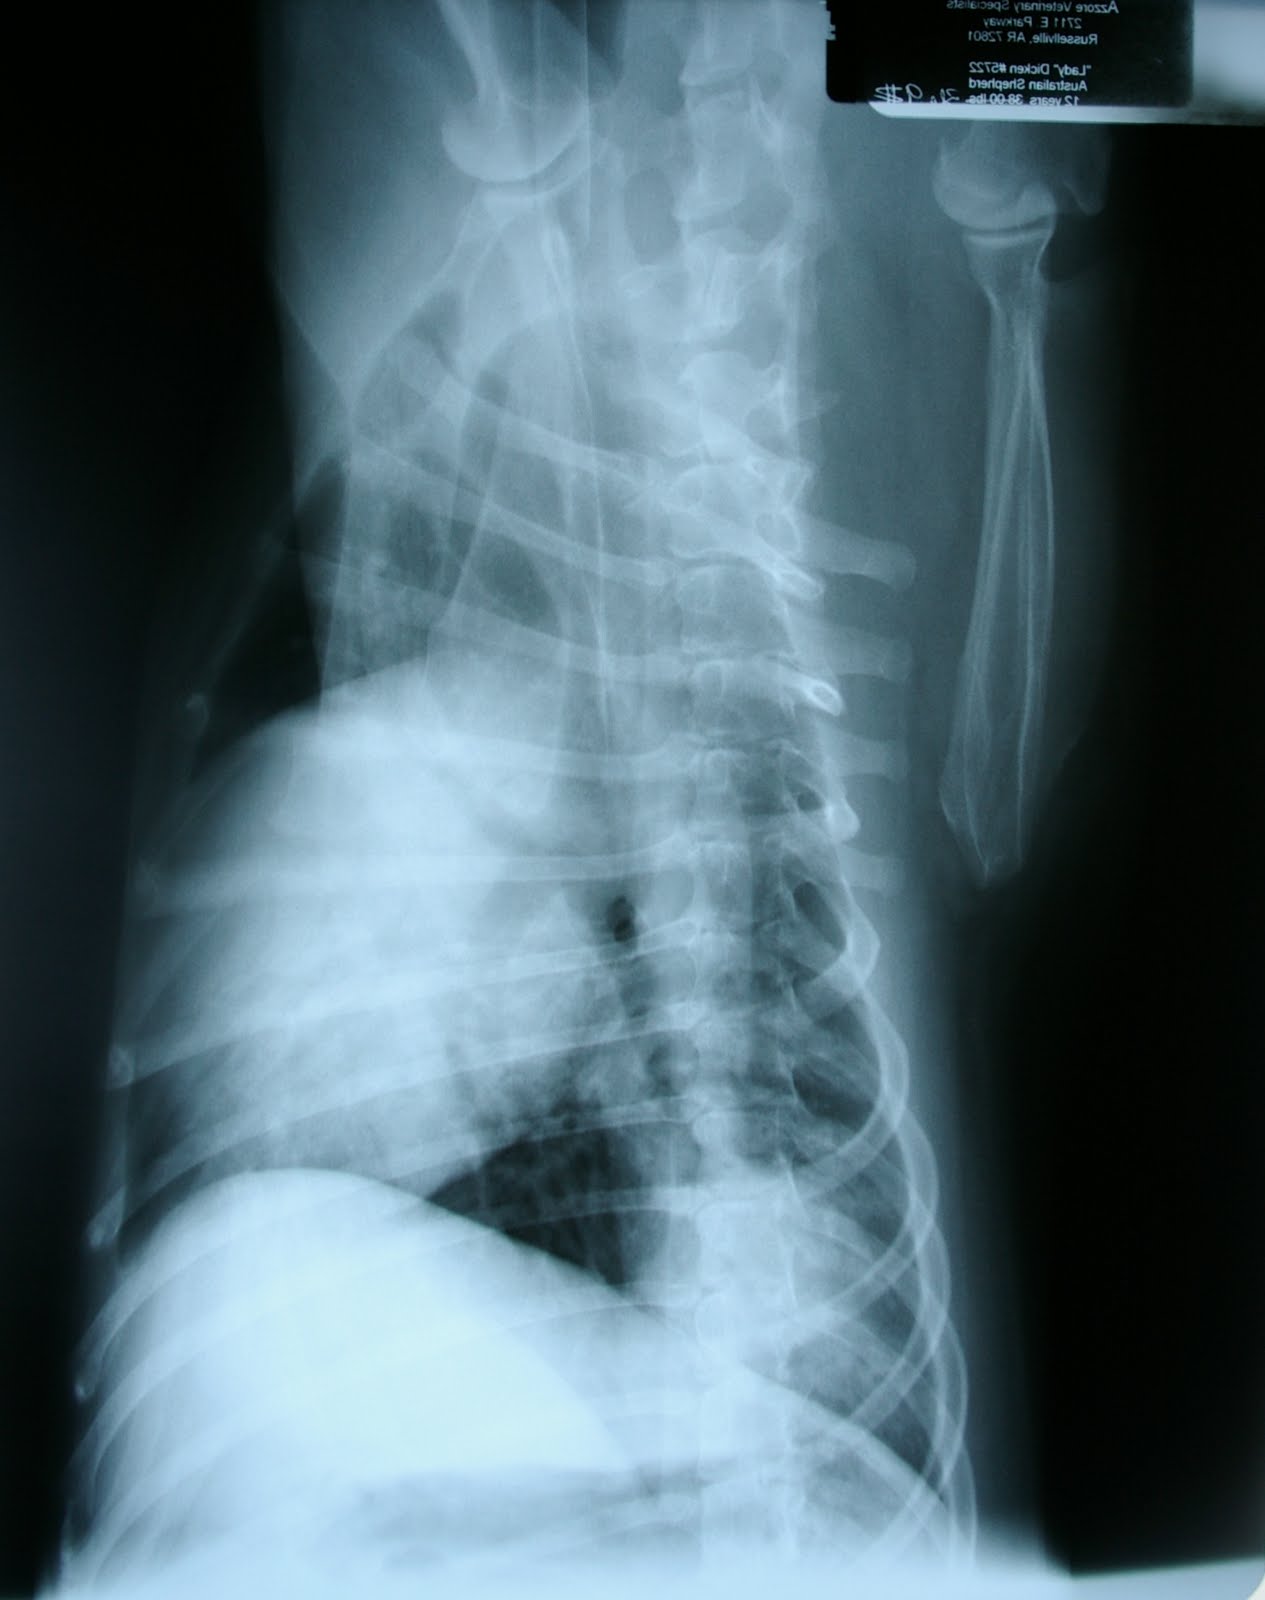

Brownie came to us at the beginning of the month for rear limb paresis (paralysis). He had been treated over the weekend for sudden onset of pain and then paralysis over the weekend at the Fort Smith Animal Emergency Center with no improvement. He came to Azzore Veterinary Specialists on Wednesday unable to walk or support himself at all on his hind legs, but deep pain was still present. Prognosis for Brownie was fair post surgery.TREATMENT:

Myelogram: X-rays with contrast medium (iohexol) showed column thinning from L3-L5 and a slight deviation of the cord to the left at L4-5. While Dr. Dew determined that a hemilaminectomy would be beneficial, due to cord swelling, Brownie's prognosis was downgraded to guarded.

Hemilaminectomy: A large amount of disc material was removed at L4-5, and durotomy (incision to the outer covering of the spinal cord) performed to relieve pressure.